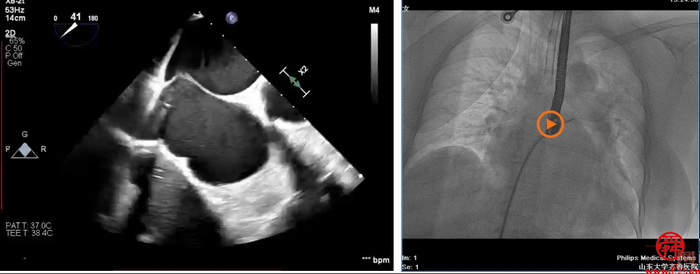

术中,患者全麻后,在经食道超声和DSA的引导下,经股静脉建立路径,穿刺房间隔,瓣膜夹通过输送系统送入左心房,顺利到达二尖瓣病变区域。在经食道超声和DSA的辅助下,术者通过反复评估二尖瓣反流位置、抓捕位置、反流程度、巧妙夹合,在A2/P2区植入2枚DragonFly夹子。术后,患者反流程度从4+转至1+,手术取得成功。

该患者为进一步治疗就诊于齐鲁医院心血管内科,初步诊断为酒精性心肌病、二尖瓣反流(重度)、射血分数减低型心力衰竭、心功能Ⅲ级(NYHA分级)、心律失常、短阵室性心动过速、冠状动脉粥样硬化等。术前心脏彩超经胸超声检查提示,二尖瓣重度反流4+,二尖瓣反流束宽度1.87cm,缩流颈宽度VC=0.7cm,有效反流口面积(EROA)=0.47,二尖瓣瓣口面积5.0cm。